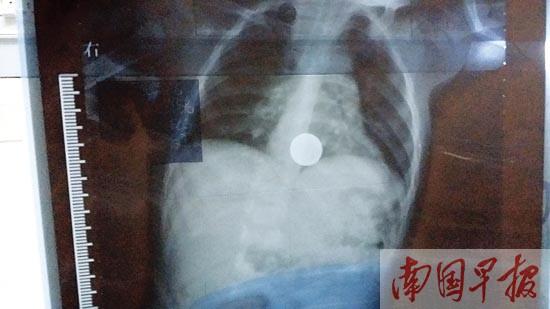

胸腹X线片显示男童吞下的硬币。 记者 刘冬莲摄

小蒙今年两岁,从宾阳县到南宁求医。据蒙妈妈说,孩子是8月25日玩耍时吞下硬币的,她马上带孩子到县医院就诊。胸腹X线片显示,孩子的胸部赫然出现一个圆形物品。医生称,这是胃里的硬币成像。为进一步求证,蒙妈妈带孩子到南宁一家大医院就诊,结果与县医院拍的片一样,硬币的位置没变。随后,蒙妈妈带孩子到广西中医药大学附属瑞康医院就诊。

“虽然误吞的异物是圆形,从肠道排出的几率很大,但也有可能因为硬币直径过大而引发肠梗阻。”朱医生说,等孩子麻醉苏醒后,还会再拍一个胸腹X线片,以确认硬币到了哪里,并密切观察孩子有无肠梗阻症状,然后再视情制定治疗方案,“这已是近段时间我们接到的第三个吞食硬币的儿童了”。